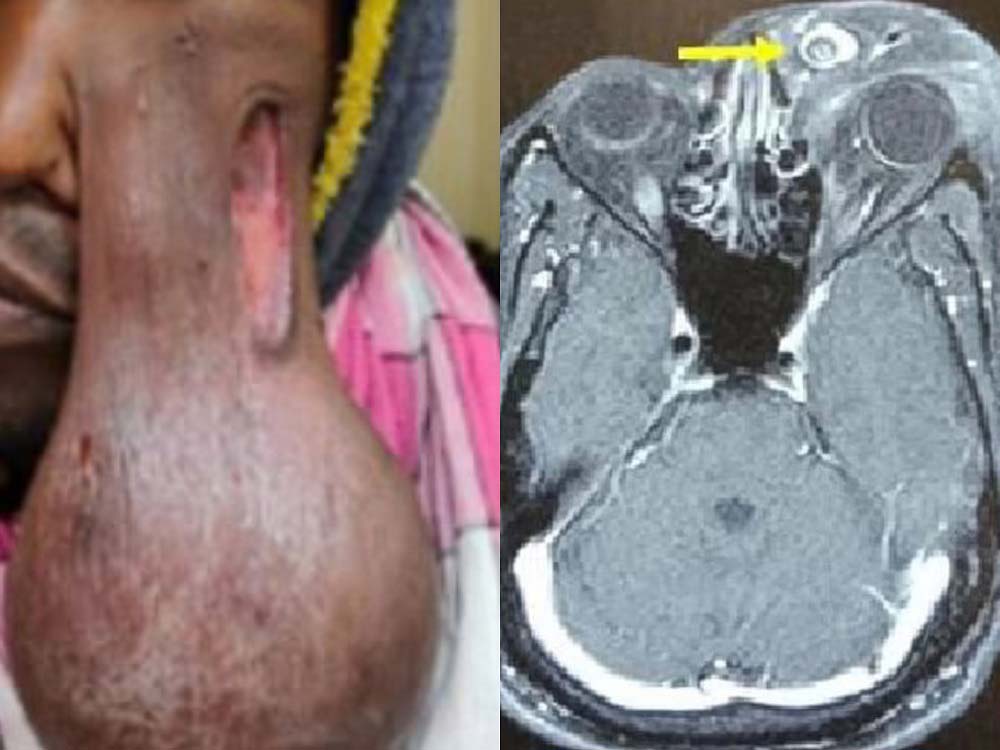

지난 3일(현지시각) 영국 데일리메일 등 외신은 지난 10월 영국의학저널(BMJ)에 보고된 인도 남성의 사례를 보도했다. 사례 속 남성은 5년 전 왼쪽 눈꺼풀에 부종이 생겼다. 수년간 이 덩어리는 크기를 키웠고, 가슴까지 내려올 정도로 크기가 커졌다. 눈꺼풀에서 뻗어나간 덩어리 때문에 남성은 왼쪽 시야가 가려지기도 했다. 결국 그는 덩어리를 제거하기 위해 병원을 방문했다. 의료진은 남성이 ‘리노스포리디움 세베리(Rhinosporidium seeberi)’라는 기생충에 감염돼 눈 주위 조직이 염증을 일으켜 종양 덩어리로 이어졌다고 추정했다. 다만, 감염 경로와 시기에 대해서는 알려지지 않았다. 의료진은 기생충 감염 후 ‘혈관섬유종(angiofibroma)’이 발생했다며 “기생충 감염과 종양이 동시에 발생하는 일은 드물다”고 보고했다. 종양의 크기는 15cm × 14cm였다. 의료진은 혈관색전술로 과다 출혈을 막은 뒤 수술로 종양을 제거했다. 수술 3개월 후 남성은 완전히 회복했고 시력도 되찾았다.

사례 속 남성이 감염된 리노스포리디움 세베리는 주로 열대 및 아열대 지역에서 발견되는 물 기생충으로, 주로 인도나 스리랑카에서 감염될 때가 많다. 이 기생충은 연못, 강 같은 민물 환경에서 감염되기 쉬우며, 인간과 동물 모두 감염될 수 있다. 감염될 경우 코, 눈, 구강 등에 영향을 주며 종양 형태의 병변을 일으킨다. 비정상적인 출혈이나 얼굴 비대칭을 유발하기도 한다. 항생제나 항진균제보다는 외과적 절제로 치료하는 편이다.

사례에서 남성이 겪은 혈관섬유종은 혈관과 섬유 조직으로 이뤄진 양성 종양을 말한다. 혈관섬유종은 콜라겐, 섬유모세포, 혈관이 과도하게 성장해 발생한다. 환자 중에는 유전자 변이로 인해 발병하는 경우가 대부분이다. 혈관섬유종이 생기면 따가운 느낌을 받고, 출혈이 생길 때도 있다. 혈관섬유종은 종양의 크기나 위치에 따라 치료법이 다르다. 보통 외과적 절제를 진행하지만, 종양에 혈관이 많아 과다 출혈의 위험이 있기 때문에 사례처럼 수술 전 혈관색전술로 출혈을 줄이기도 한다. 혈관색전술은 혈관을 막는 시술로, 출혈이 발생하는 부위의 상위 혈관을 막아 종양을 죽이는 치료법이다.